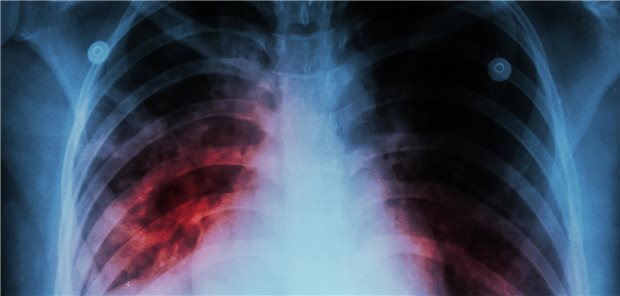

Neue Strategie zur Tuberkulose-Früherkennung

Arznei gegen Tuberkulose